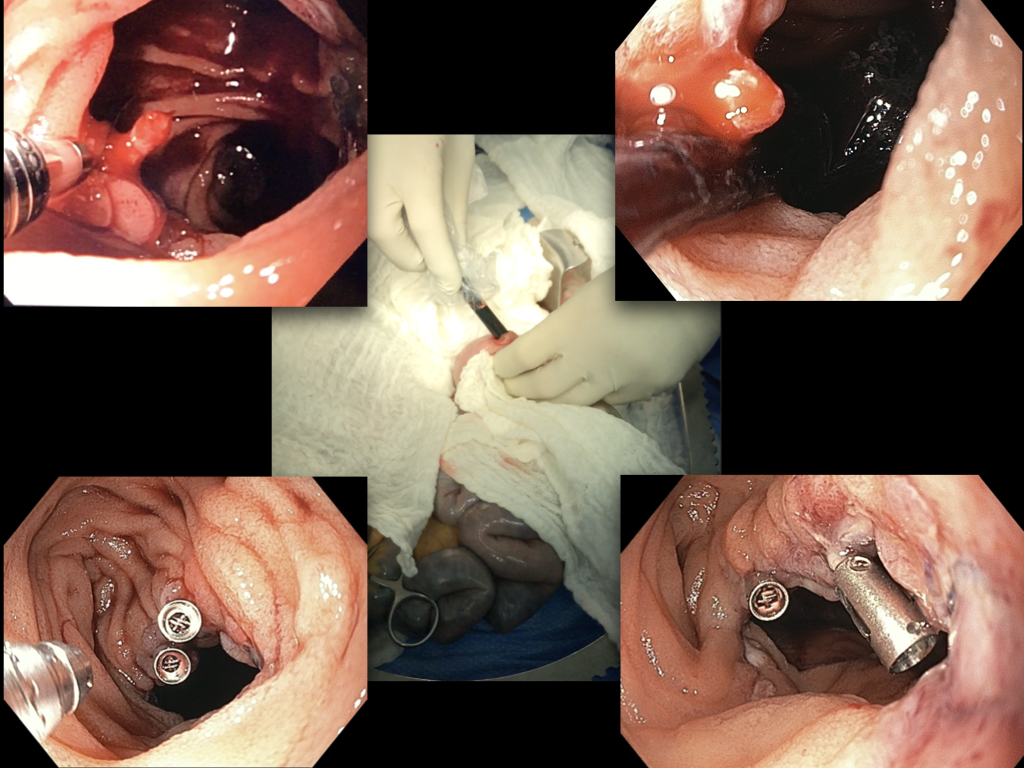

In both cases, a hybrid approach was performed. This approach involved a laparotomy and an intraoperative endoscopy through a small enterotomy in the jejunum distal to the duodenal anastomosis. Active bleeding from the enteric anastomosis was found in both cases, which was resolved by an endoscopic approach without the need for dismantling the duodenal anastomosis.

Conclusions: This hybrid approach for the management of bleeding from the enteric anastomosis site allows for control of the bleeding without the need for dismantling the anastomosis. With the assistance of an experienced endoscopist it is a fast, safe and reliable approach.